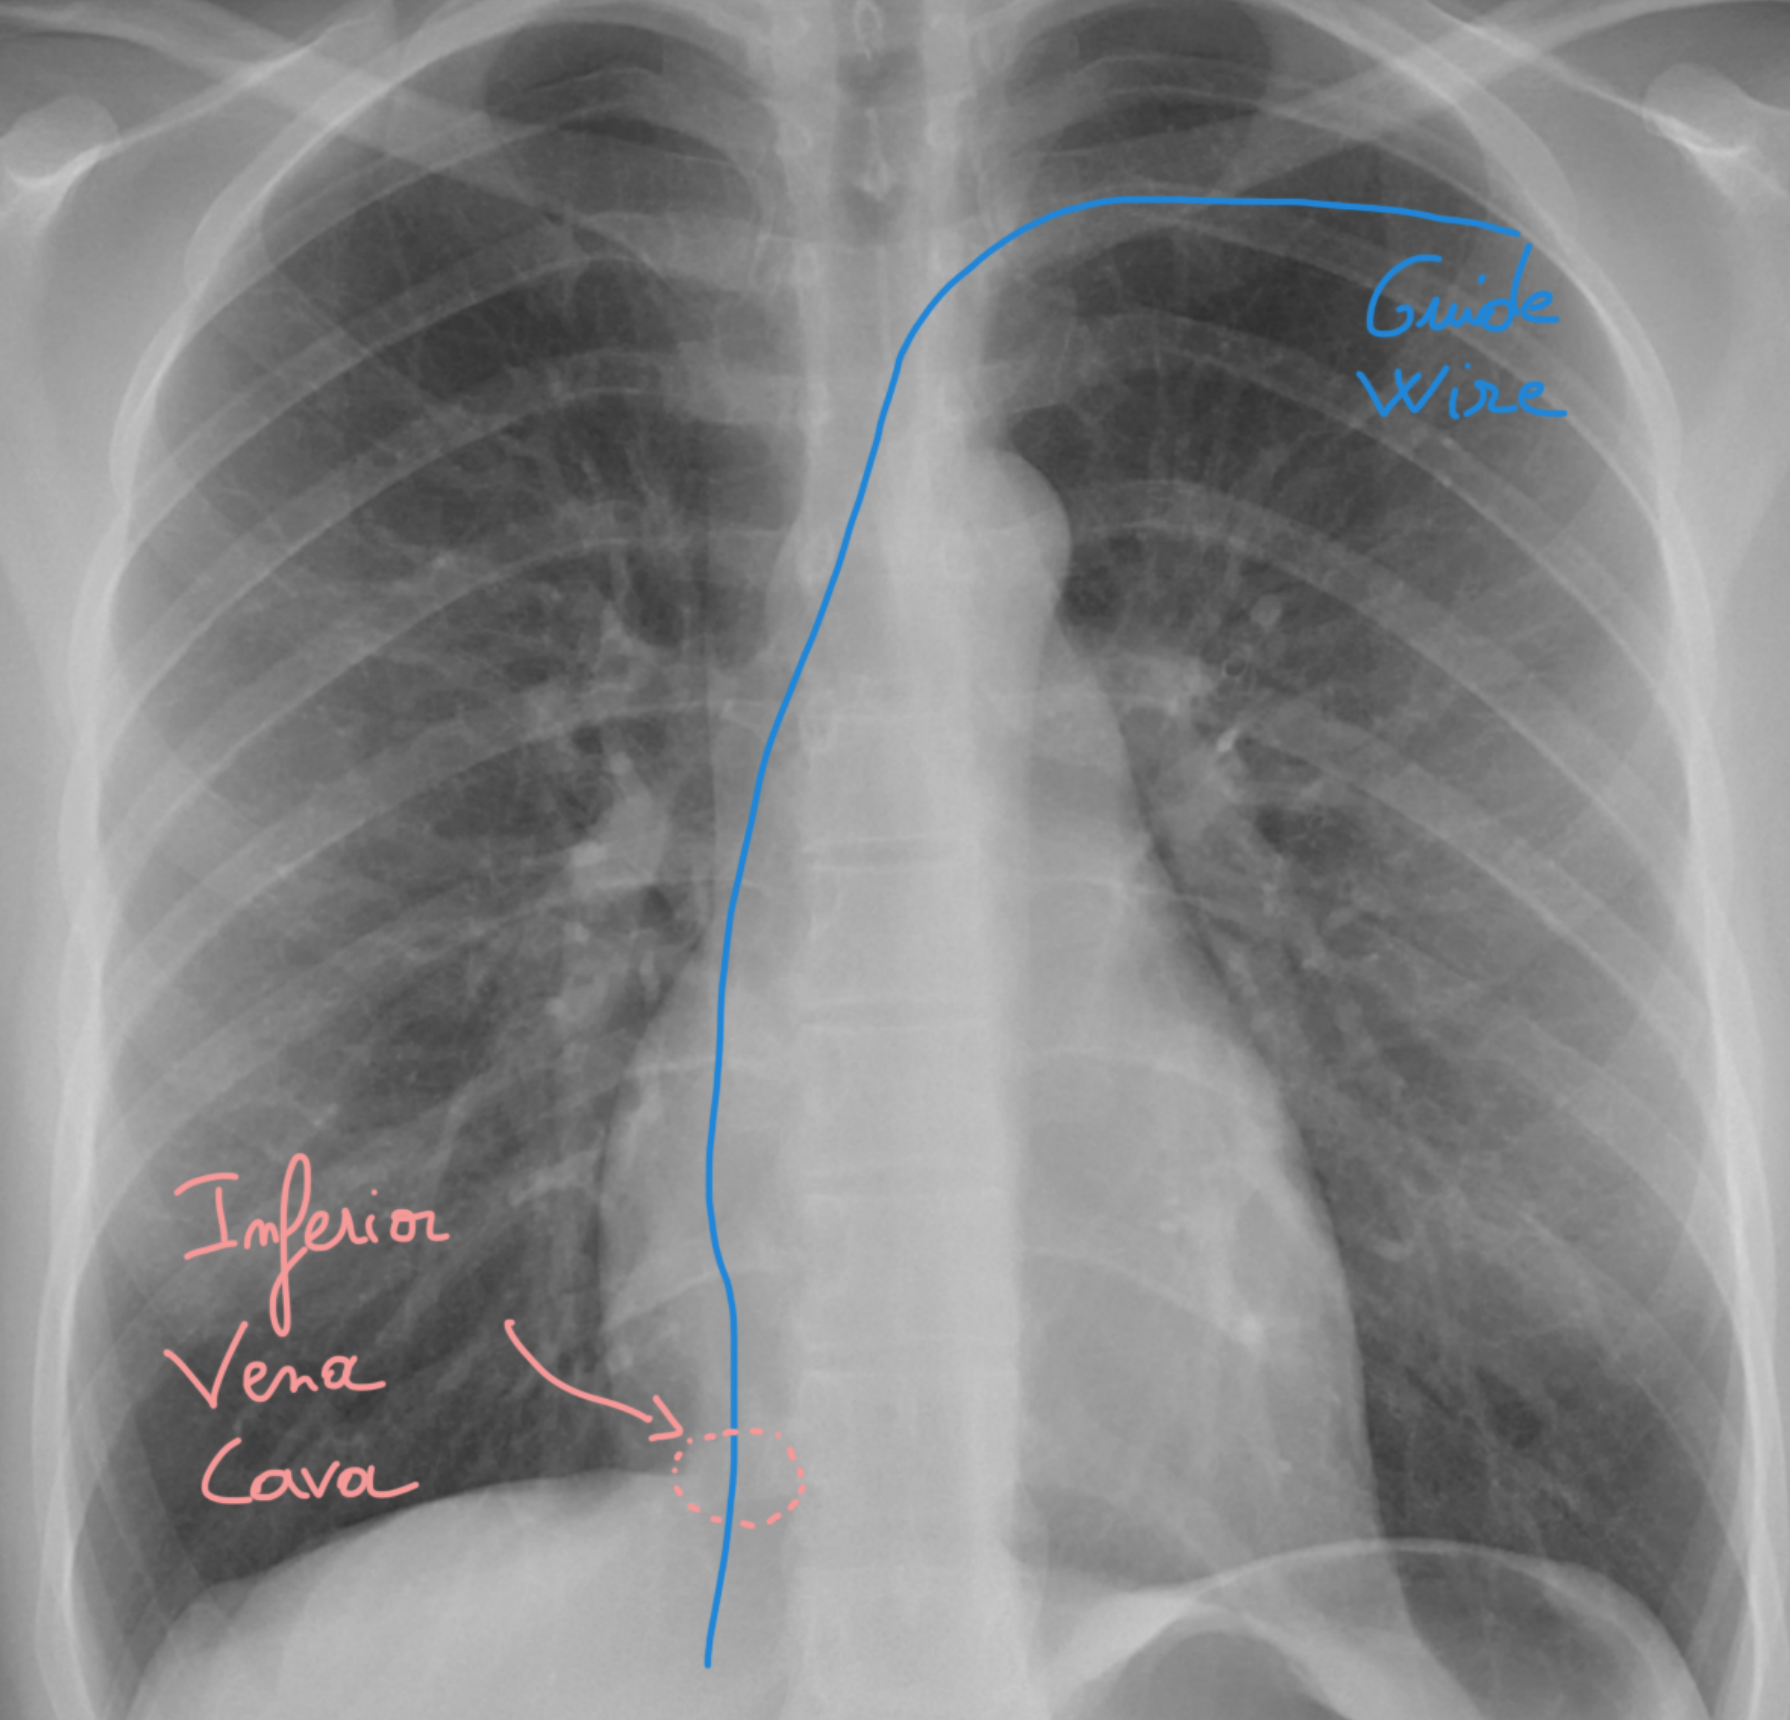

๐Ÿ” Step 11: Confirm the vein before dilation! โš ๏ธ

Always check that your needle is heading into the inferior vena cava ๐Ÿซโฌ‡๏ธ to be 100% sure youโ€™re in the vein before you start dilating.

๐Ÿšซ Never dilate if youโ€™re not certain youโ€™re in the vein โ€” this is your golden rule! ๐Ÿ…

Think of it like checking the GPS ๐Ÿ›ฐ๏ธ before taking a steep downhill road: one wrong turn and itโ€™s trouble!